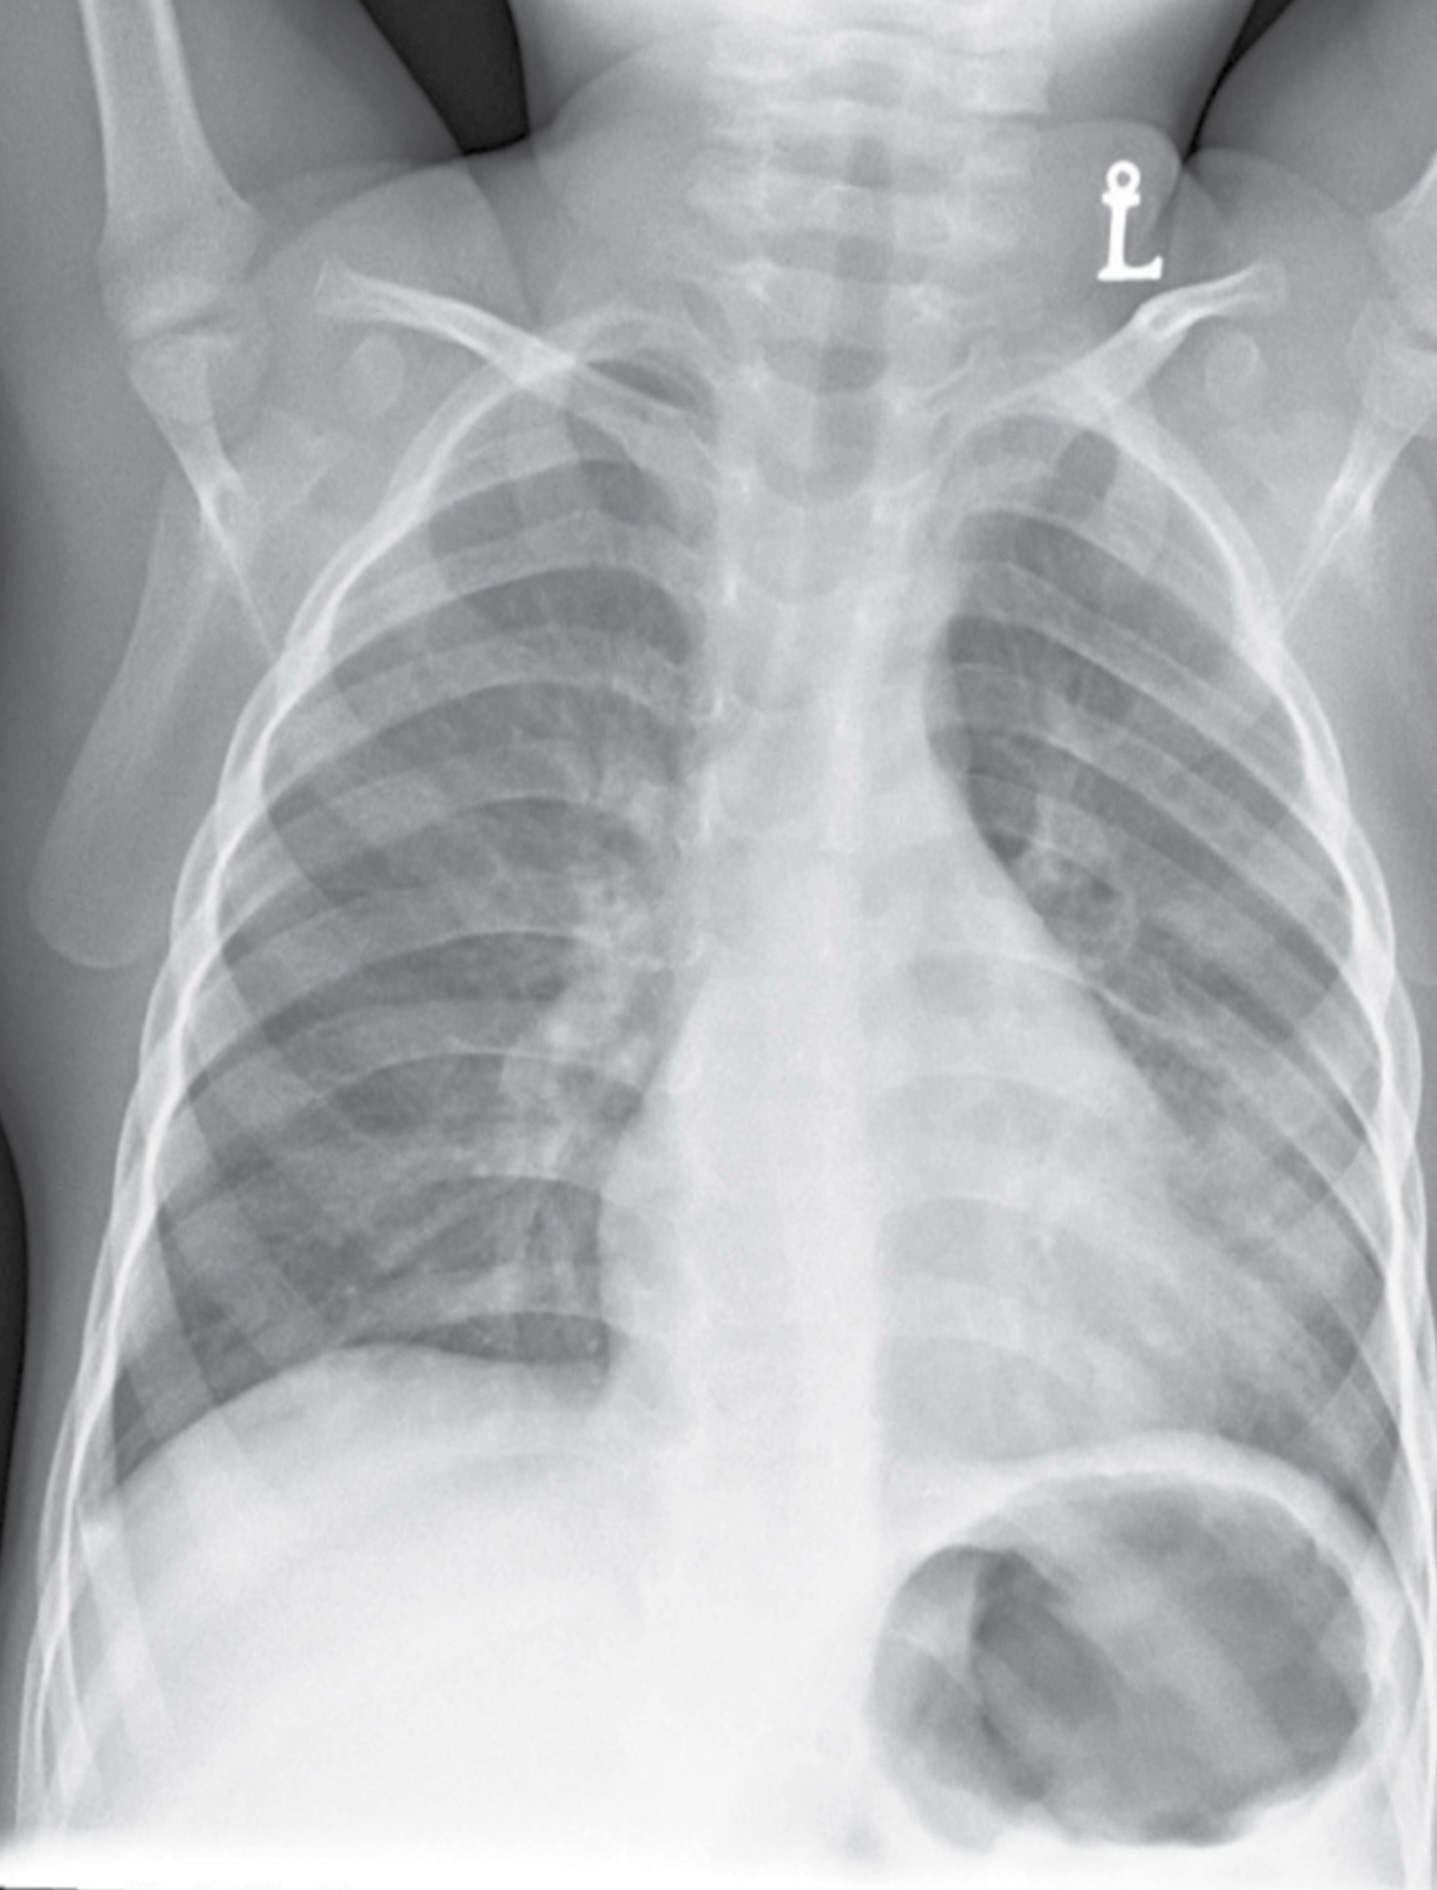

Мати чотирьохрічного хлопчика, який скаржиться на кашель та лихоманку, звернулась до лікарні. При обстеженні температура тіла підвищена, тахіпное. Аускультативно над лівою легенею вислуховуються вологі хрипи.

На дані рентгенограмі ОГК в прямій проекції пацієнт дещо ротований. Відмічається ніжне затемнення у нижніх відділах лівої легені. Ліва межа серця не чітка. Куполи діафрагми чіткі. Права легеня без інфільтративно-вогнищевих змін. Кістково-деструктивні зміни відсутні.

Висновок: на даній рентгенограмі спостерігається лівобічна пневмонія.